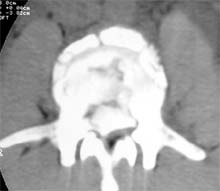

患者男性,30岁,腰3骨折,截瘫

CT显示腰3椎体爆裂,骨块凸入椎管压迫硬膜囊